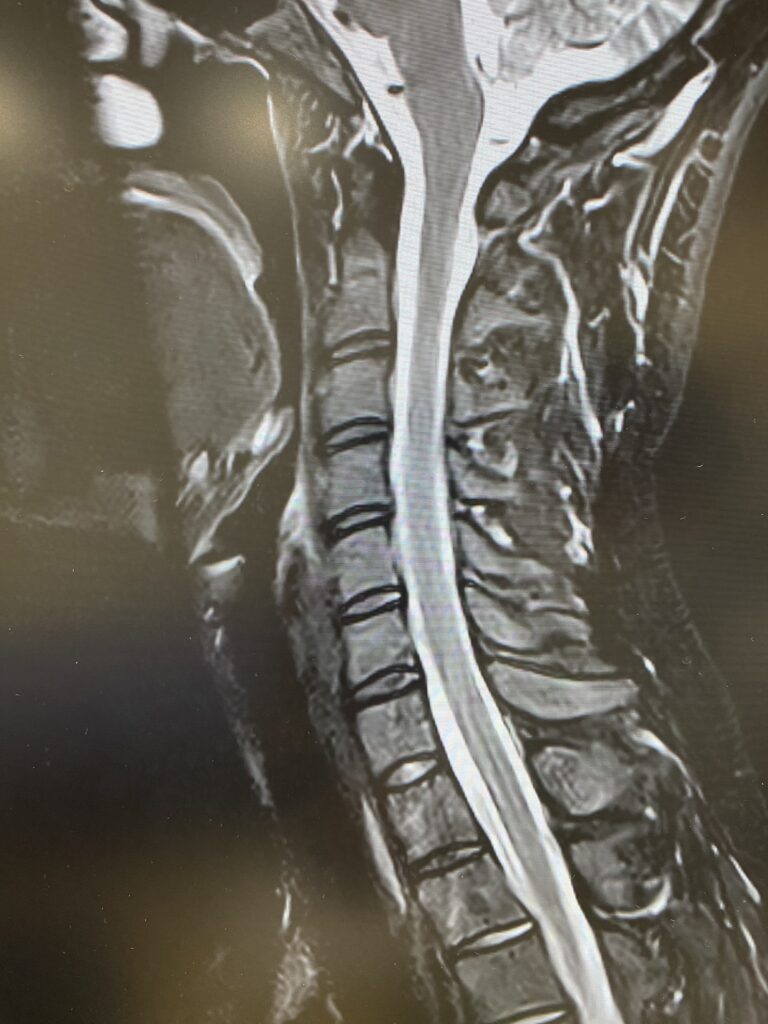

1.5T MRIへの更新作業が完了しました。

9月上旬から休止していたMRIの撮影が可能となり、画像精度が飛躍的に向上します。